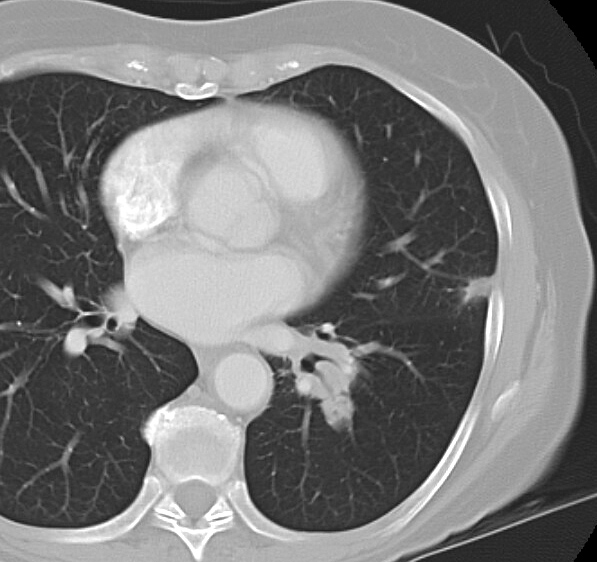

Gallery Mediastinum Lymphoma 8d

8d